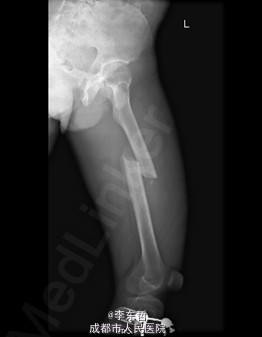

患者男,19岁,因“车祸伤致左下肢活动障碍5小时”入院。5小时前,患者骑电瓶车不慎与另一电动摩托车相撞倒地,当即感左大腿疼痛,畸形,活动受限,右小腿皮肤挫伤、出血,无头晕头痛,无大小便失禁。就诊于当地医院,检查提示:左股骨中段横行骨折。急诊行左大腿夹板外固定,右小腿清创缝合术,术后未进一步治疗,患者为进一步诊治来我院,急诊以左股骨中段骨折收入我科。 自患病以来,患者一般情况尚可,精神睡眠可,小便正常,大便未解。

查体:左大腿夹板固定,肿胀明显,短缩、畸形,右小腿内前方可见一长约5cm创口,已缝合,内植引流条一根,无明显肿胀。左大腿中段环周压痛,可扪及骨折断端,右小腿无明显压痛,双下肢感觉正常。左膝及髋关节明显活动受限,左足背及右下肢活动正常。 辅查:外院X片示:左侧股骨中上段可见骨质断裂征象,断端分离、错位、重叠,周围软组织肿胀;双侧胫腓骨、左膝关节各骨及左踝关节未见确切骨质断裂征象。

初步诊断:1、左股骨中段横行骨折,2、右小腿皮肤软组织裂伤清创缝合术后。 诊疗计划:1、向患者及家属交待病情及注意事项。2、向上级医生汇报患者病情。3、完善术前相关检查。4、给予皮肤牵引、抬高患肢等对症处理。5、拟进一步手术治疗。6、密切观察病情变化,根据病情及时处理